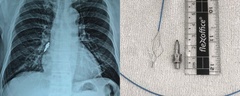

Các bác sĩ tại Bệnh viện Đa khoa Bạc Liêu, tỉnh Cà Mau vừa gắp thành công một chiếc bông tai kim loại mắc trong thực quản bé gái 8 tháng tuổi.